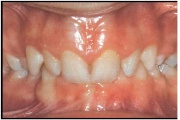

Sügav hambumus

ülemised eeshambad katavad täielikult alumisi